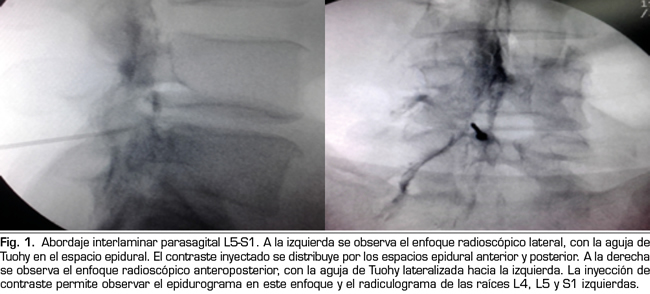

Los procedimientos fueron realizados en sala de operaciones. Con el paciente en posición decúbito ventral se colocó una vía venosa periférica. La asepsia se efectuó con clorhexidina alcohólica y la anestesia local con lidocaína al 0,5 %. En la técnica interlaminar parasagital se utilizaron agujas de Tuohy números 18, 3½ o 4¾ pulgadas según la complexión física del paciente. Con enfoque radioscópico anteroposterior, se introdujo la aguja en los espacios interlaminares, L4/L5 o L5/S1, utilizando la técnica en visión túnel, parasagital homolateral del lado correspondiente al dolor radicular (Figura 1). Se realizó pérdida de resistencia con suero fisiológico. En el enfoque lateral se administró una inyección de 4 ml de contraste (Omnipaque®) y se consignó la presencia de epidurograma anterior, posterior o ambos (Figura 1). En el enfoque anteroposterior se consignaron las características del radiculograma y del epidurograma (Figura 1). Luego se administró un frasco de betametasona (12 mg de una mezcla de fosfato y acetato de betametasona, en 2 cc de solución) más 3 cc de lidocaína al 0,5 % (total 5 cc de solución). Se evaluó la calidad técnica del bloqueo con elementos clínicos como la presencia de parestesias o dolor concordante durante la inyección, y datos radiológicos como la presencia de radiculograma y de epidurograma anterior (Figura 1). En el grupo tratado con betametasona por vía epidural transforaminal se utilizaron agujas de Quincke números 22, 3½ o 4¾ pulgadas con enfoques radiológicos oblicuo, lateral y anteroposterior. El punto objetivo en posición oblicua fue la zona subpedicular, en enfoque lateral el ángulo anterosuperior o techo del neuroforamen, en el llamado triángulo de seguridad en el enfoque anteroposterior (Figura 2). La inyección de contraste fue equivalente a la realizada en el grupo interlaminar, debiéndose obtener radiculograma y epidurograma tras la inyección (Figura 2). La solución de betametasona fue la misma que la utilizada en el grupo interlaminar, inyectándose la totalidad de la solución por el neuroforamen elegido, o la mitad de la solución en cada neuroforamen cuando por criterios clínicos se decidió la inyección en dos niveles.

En 21 de los 26 procedimientos realizados por el acceso interlaminar parasagital se evaluó la calidad técnica de la inyección epidural de esteroides. En 15 (71 %) se obtuvo epidurograma anterior, esto es, alcance de la solución en la cara ventral del espacio (Figura 1 izda.); en 17 (85 %) el paciente refirió dolor o parestesias en el territorio radicular durante la inyección, y en 12 (60 %) se observó radiculograma junto a la imagen característica de epidurograma.